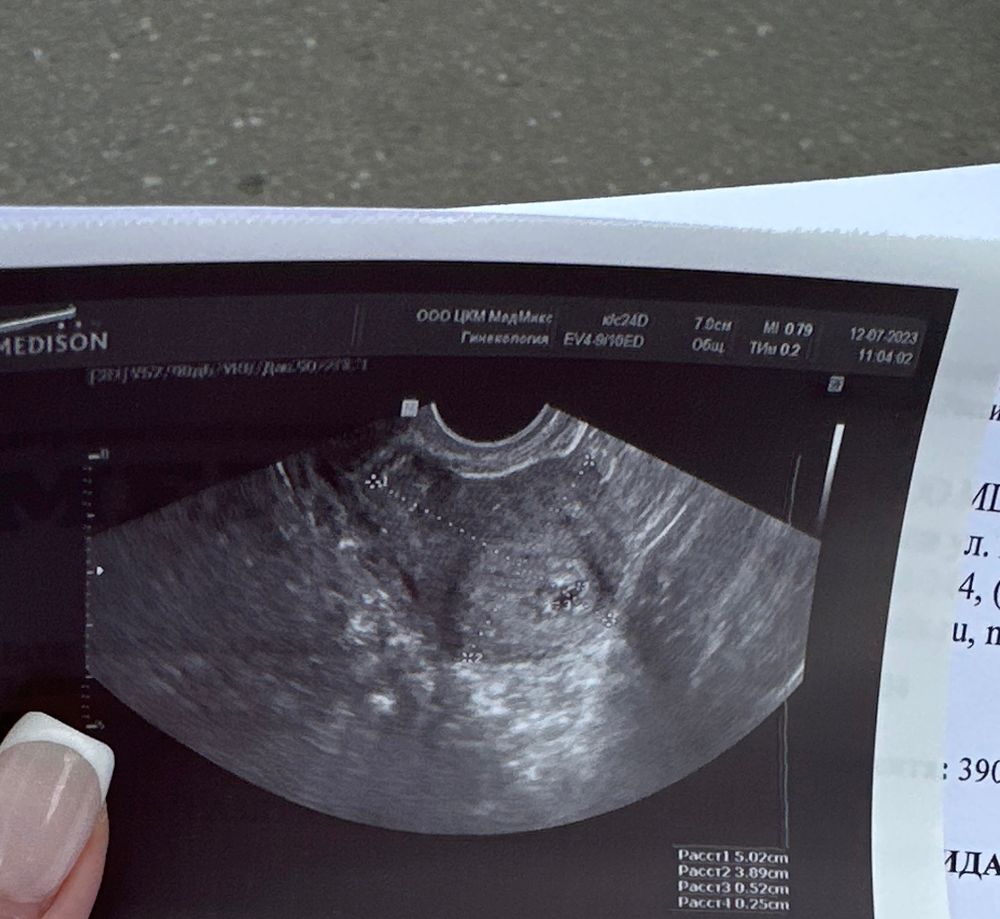

Всем привет ,до субботы мои нервные клетки бы наверное не выдержали ,поэтому ,я сегодня рано утром записалась к врачу на узи ,сегодня 5 недель ровно ,еду я к врачу и волнение ,потом зашла в кабинет разъясняю ,а у меня дрожь в голосе ,ноги трясутся руки тоже ,не знаю зачем так нервничала ,просто боялась услышать ,отрицательный ответ .В итоге вот ответ ,на мои переживания

как-то так , я услышала заветные слова ПЯ В МАТКЕ ,и просто выдохнула и разревелась ,я увидела свою маленькую креветочку , хотя она даже сейчас больше как точечка❤️❤️❤️❤️ ,завтра пойду сдам анализы ,чтобы посмотреть ,как у меня вообщем дела ,надеюсь все пройдёт хорошо